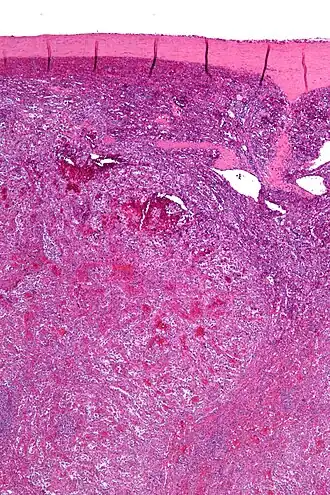

Un angiome splénique à cellules littorales est une lésion vasculaire rare et généralement bénigne[n 1] qui se développe exclusivement à partir des cellules littorales des sinus de la pulpe rouge de la rate[1]. Décrit pour la première fois en 1991 par Falk et al.[2],[3], il survient indépendamment de l'âge ou du sexe du patient[4].

Les lésions vasculaires, réalisent des lacunes caverneuses anastomotiques au sein de la pulpe rouge. Ces lacunes sont bordées par des cellules endothéliformes ou des cellules plus volumineuses[4]. Les cellules néoplasiques expriment à la fois les propriétés épithéliales et histiocytaires basées sue celles de leur cellule d'origine, les cellules du littoral splénique[2].

À l’immunohistochimie, ces cellules sont positives aux marqueurs vasculaires et macrophagiques. Ces cellules sont reconnues par l’anticorps anti-CD31 et par l’anticorps anti-CD68[4].

On peur prélever un échantillon de la tumeur via une aspiration à l'aiguille fine. Histologiquement, on observe de petits canaux vasculaires produisant des anastomoses et des espaces kystiques avec des projections papillaires[5].